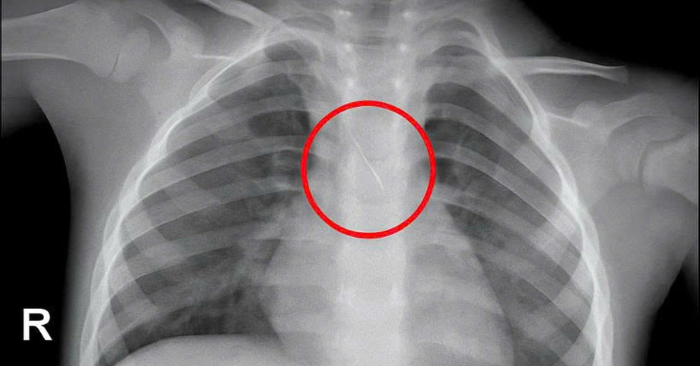

Bệnh viện Đa khoa tỉnh Quảng Trị cho biết bệnh nhi N.Q.T.Đ. (3 tuổi, trú xã Cửa Việt) được đưa đến trong tình trạng ho dồn dập, khó chịu và không rõ nguyên nhân. Ngay sau thăm khám, bác sĩ chỉ định chụp phim và phát hiện một dị vật kim loại nằm ở vị trí carina – điểm chia đôi khí quản của cơ thể.

Hình ảnh cho thấy một đầu kim nhọn cắm vào đoạn 1/3 dưới khí quản, đầu còn lại mắc tại phế quản góc trái. Vị trí này cực kỳ nguy hiểm, có thể khiến trẻ bị tắc nghẽn đường thở, xẹp phổi, viêm phổi, tràn khí màng phổi hoặc tử vong nếu không được can thiệp kịp thời.